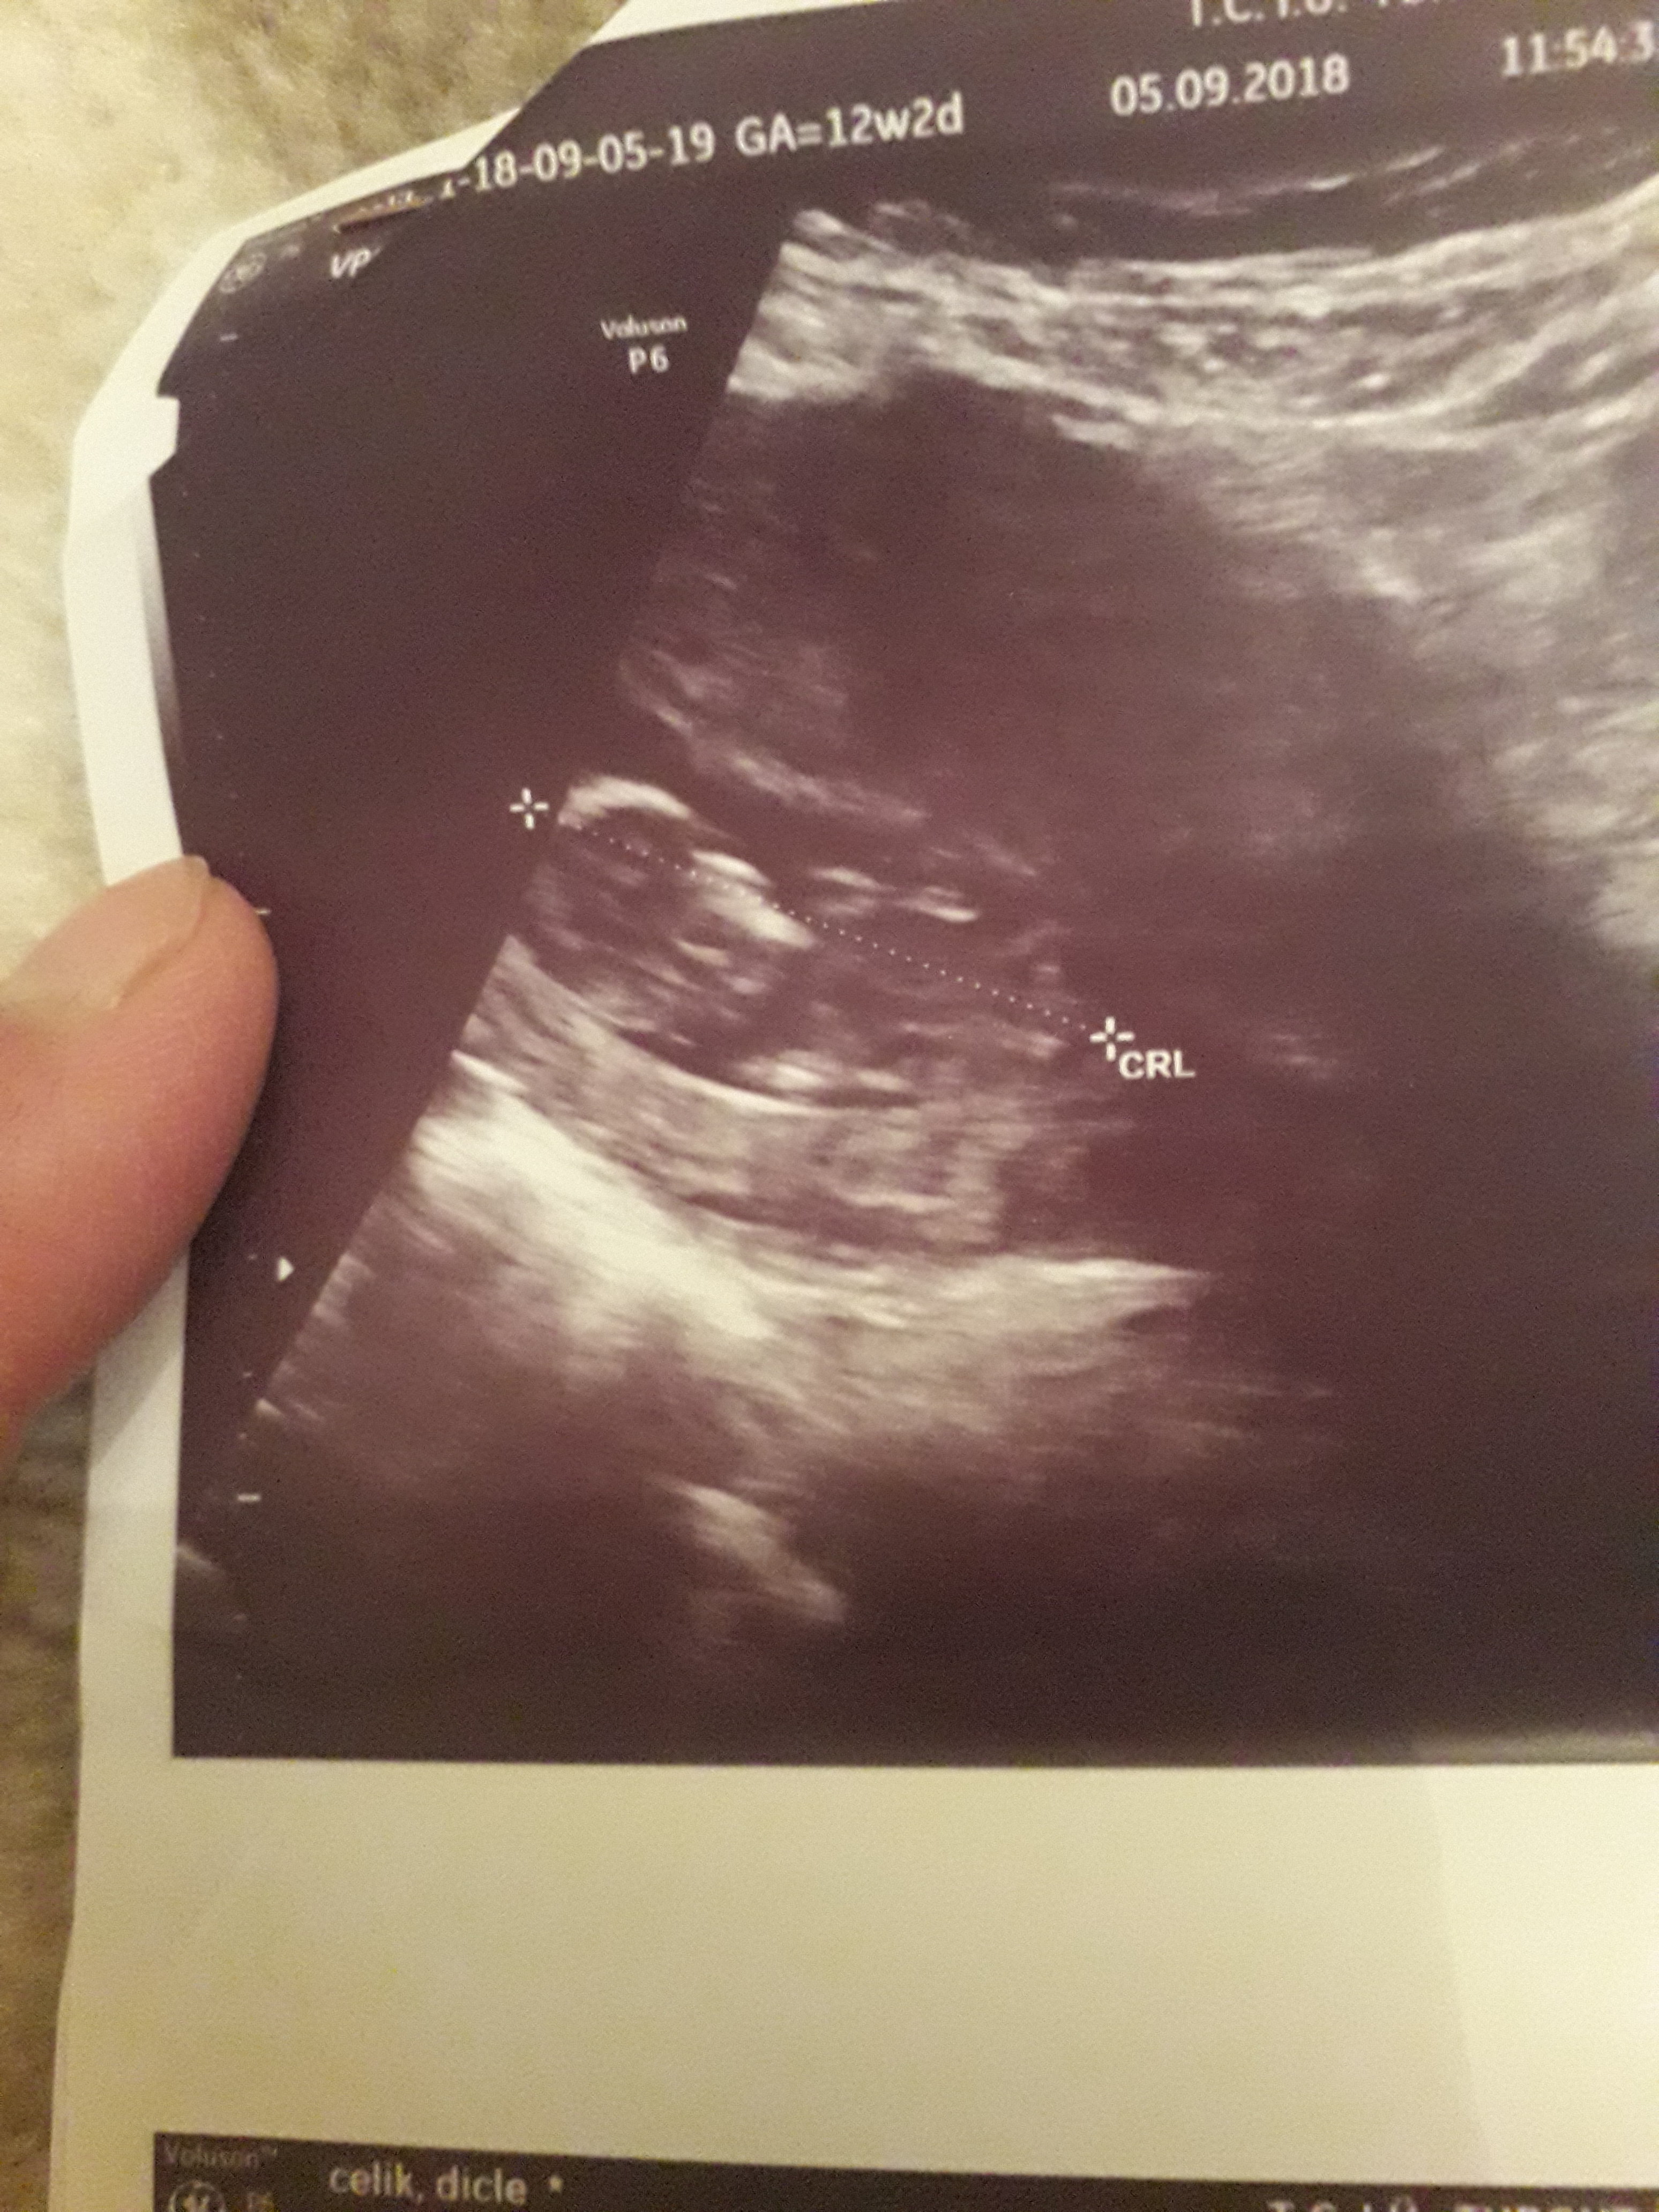

Banada yorum.yapin lutfen 12 haftaligiz

1,7 MB · Görüntüleme: 764

Nub teorsisi için cinsiyet tahmininde yorum isteyen arkadaşlar lütfen uyarımızı dikkate alın. Ultrason görüntüleri elinize ilk verildiği gibi net olmaz. Sık sık ışığa maruz kaldığı için görüntü kalitesi bozuluyor dolaysıyla bizlerde değerlendirme yapamıyoruz. Sizlere yorum yapabilmemiz için görüntü kalitesi aşağıdaki linkte yer alan görseller gibi olmalıdır. Ayrıca Bebeğin cinsiyeti net olarak 18-19-20. haftalarda belli olur..

Merhaba, yüklediğiniz görsellerde nub çıkıntısı anlaşılmıyor , dolaysıyla değerlendirme yapamıyoruz.. Görselin kalitesi aşağıdaki gibi olmaldır.. Sağlıklı gebelik süreci diliyorum.